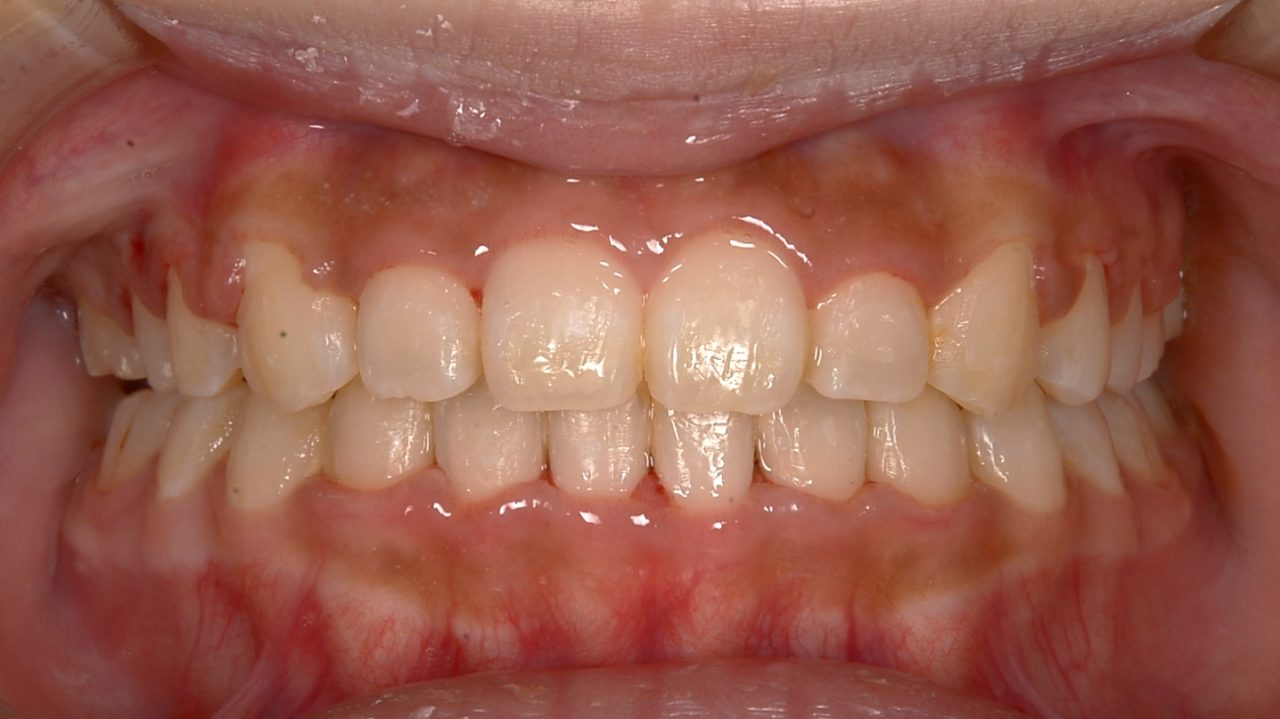

After

| 診断 | 右側アングルクラスⅡ 左側アングルクラスⅠ 正中離開 前歯オープンバイト |

| 矯正方法 | マルチブラケットによる矯正治療 矯正用アンカーを用いる |

| 矯正期間 | 14か月 |

| 備考 | 右上第1大臼歯の自発痛で来院されました。 マイクロスコープ下の精密根管治療を行えば、十分改善する見込みはありました。 しかし、14歳と若く、長期的な予後は不安でした。 前歯の歯列、咬合不正があったため、全顎矯正を提案しました。 全顎矯正ができれば、予後不良な右上第1大臼歯を抜歯して、親知らずを活かせます。 そうなれば、神経の死んだ歯はなくなり、歯の数も減りません。 14か月で矯正治療が終了したため、まだ親知らずは萌出していませんが、レントゲン的にはいい位置に来そうです。 注意深いメインテナンスを行っています。 |